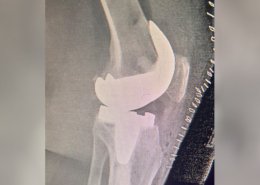

Dr. Shiva Shankaran GB is a senior specialist surgeon in knee and shoulder surgeries. He specializes in Sports injury, Arthroscopy, and Joint Replacement Surgeries. His journey is marked by a commitment to excellence and a relentless pursuit of knowledge. Physical Remedy and drugs are the first non-surgical options we look into when treating common pain, but if surgery is eventually necessary, we’ll give you the best treatment possible to help you return to your diurnal conditioning as soon as possible.

Arthroscopic & Replacement Surgeries